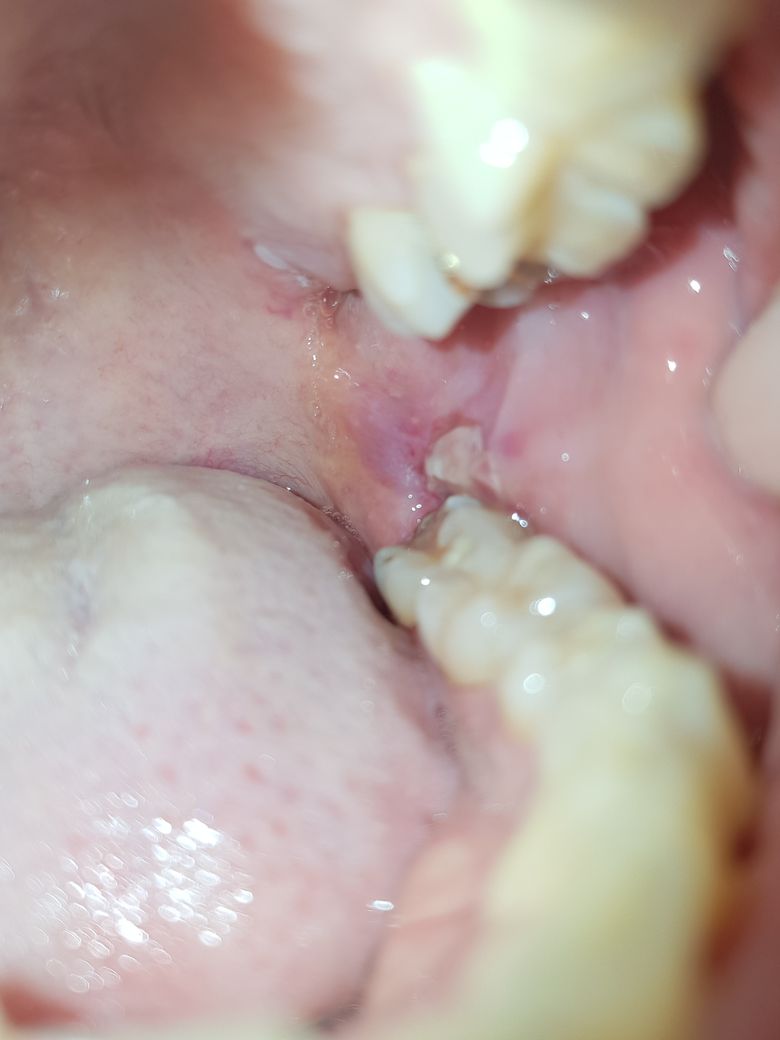

매복 사랑니 발치 후 실밥 풀었는데 구멍이 안보여요.

완전 수평 매복 발치 후 붓기가 심해서 3일만에 실밥을 제거 했습니다. 오늘이 4일차인데요. 대학병원에서 뽑은거라서 오늘 소독 받으러 갔어요.구멍이 안보여서 의사쌤한테 물어봤는데 의사쌤은 보인다고 하더라구요.

그런데 집에와서 다시 확인해봐도 안보입니다. 집에 혼자라 누구한테 봐달라고 할수도 없고요. 첨부한 사진의 잇몸벽 헐은거를 들추면 구멍이 있을까 살짝 만져봤는데 그건 그냥 헐은거였어요ㅜ 음식물 빼낼려면 구멍이 보여야 하는데 ㅠㅠ 치과에 다시 물어보는게 제일 좋긴한데, 예약이 다음주라서 5일이나 남아서 문의드립니다.

• 1번 째 사진

현재 염증이 심한 상태에서 발치를 하여 해당 부위의 회복이 염증으로 인한 피부 증식 반응 등이 일어나서 일반인들이 보기에는 보이지 않을 수 있습니다. 전문가들이 보기에는 해당 부위를 들추거나 보게 되면 조금이라도 구멍이 있습니다. 현재 상태는 전혀 문제가 되지 않으며 꼭 음식물을 배출하는 구멍이 필요한 것은 아닙니다. 따라서 걱정하지 않으셔도 됩니다.

치과용 거울로 보면 보이지만 직접보면 안보일수도 있습니다. 그리고 잇몸은 치유가 빨라서 구멍이 메꿔줫을수도 있으니 크게 걱정하실부분은 아니세요.

빨리 아문것같습니다. 구멍에 음식이 들어갔다고 굳이 후벼파시면 절대 안되고 물로 최대한 헹궈주셔야 합니다

구멍이 작아서 안보일 정도면 음식물이 많이 끼지는 않으니 걱정안해도 될것 같습니다.